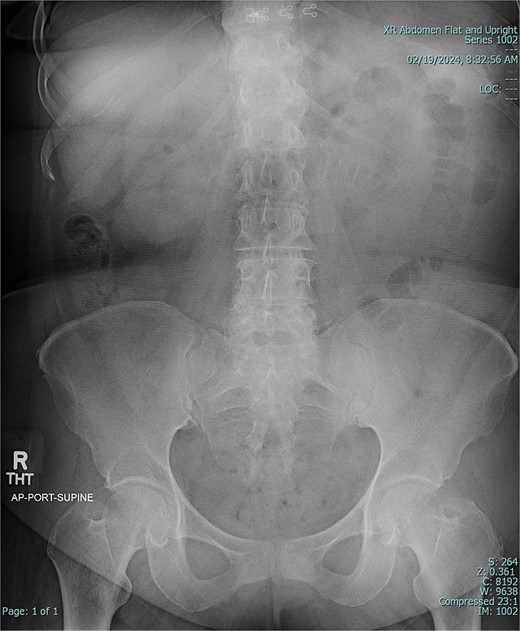

A 67-year-old female patient with a past medical history significant only for C-section, presented with 1 week of intermittent abdominal pain, distension, and nausea with vomiting. Vital signs were in the normal range. Physical exam was notable for a soft and nondistended abdomen with right lower quadrant tenderness. Laboratory studies were unremarkable. Radiological imaging (Figs 1 and 2) demonstrated a developing SBO.

Preoperative CT of abdomen in coronal view, demonstrating small bowel obstruction.